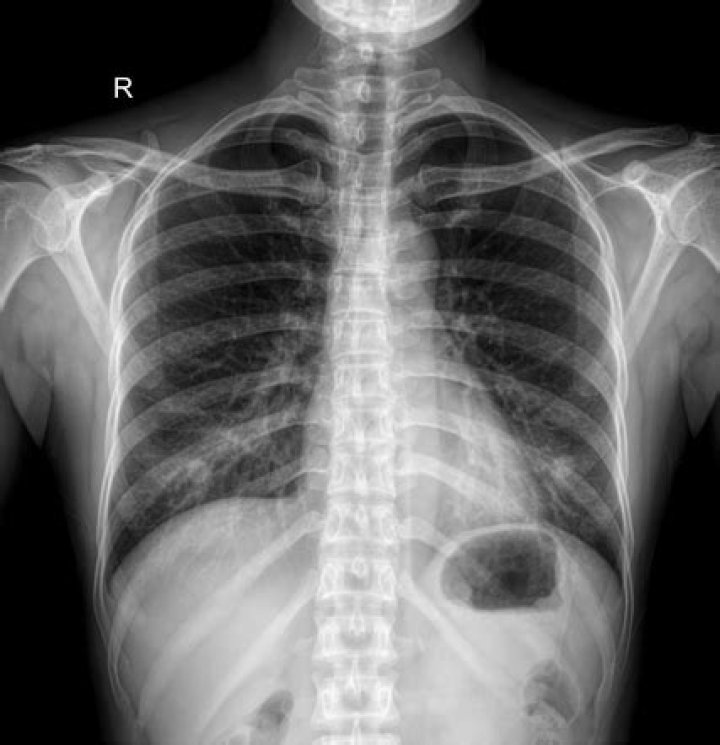

Nipple shadows refer to the silhouettes of the nipples on frontal chest radiographs, which may mimic solitary pulmonary nodules (SPNs).Click to see full